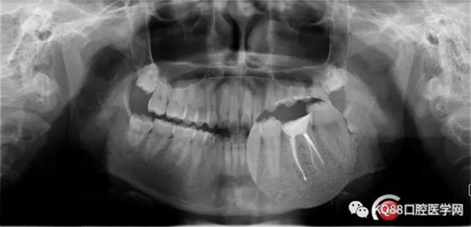

第五步:充填完成,ZOE暫時(shí)觀察。

9.png

10.png

充填完成,暫時(shí)觀察一周。下一步做牙冠延長(zhǎng),近遠(yuǎn)中打纖維樁,全冠或嵌體修復(fù)。